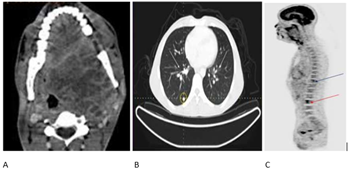

A whole-body

PET-CT was performed, revealing a large, necrotic mass involving the left

pharyngeal space, obliterating the posterior nasopharynx, and extending into

the supraglottic region with luminal obstruction. Superiorly, the mass extended

into the left infratemporal fossa and carotid space. Posteriorly, the lesion

thinned the wall of the left maxillary sinus, medially indenting the soft

palate and the posterior one-third of the tongue. The lesion showed moderate to

intense heterogeneous uptake (SUVmax: 14.6).

Bilateral sub-centimeter nodules were seen in the lungs with minimal FDG uptake

(SUVmax: 3.8), consistent with bilateral lung

metastasis. Additionally, FDG-avid lytic lesions were observed in the D11 and

L3 vertebrae with soft tissue involvement (SUVmax:

9.5 in L3 vertebra) (Figure 1).

Figure 1. PET CT: A:

Axial view of PET scan showing extent of the primary tumor; B: Axial view of

PET scan showing distant metastasis to bilateral lungs; C: Sagittal view of PET

scan showing lytic lesions at D11 (blue arrow) and L3 (red arrow).